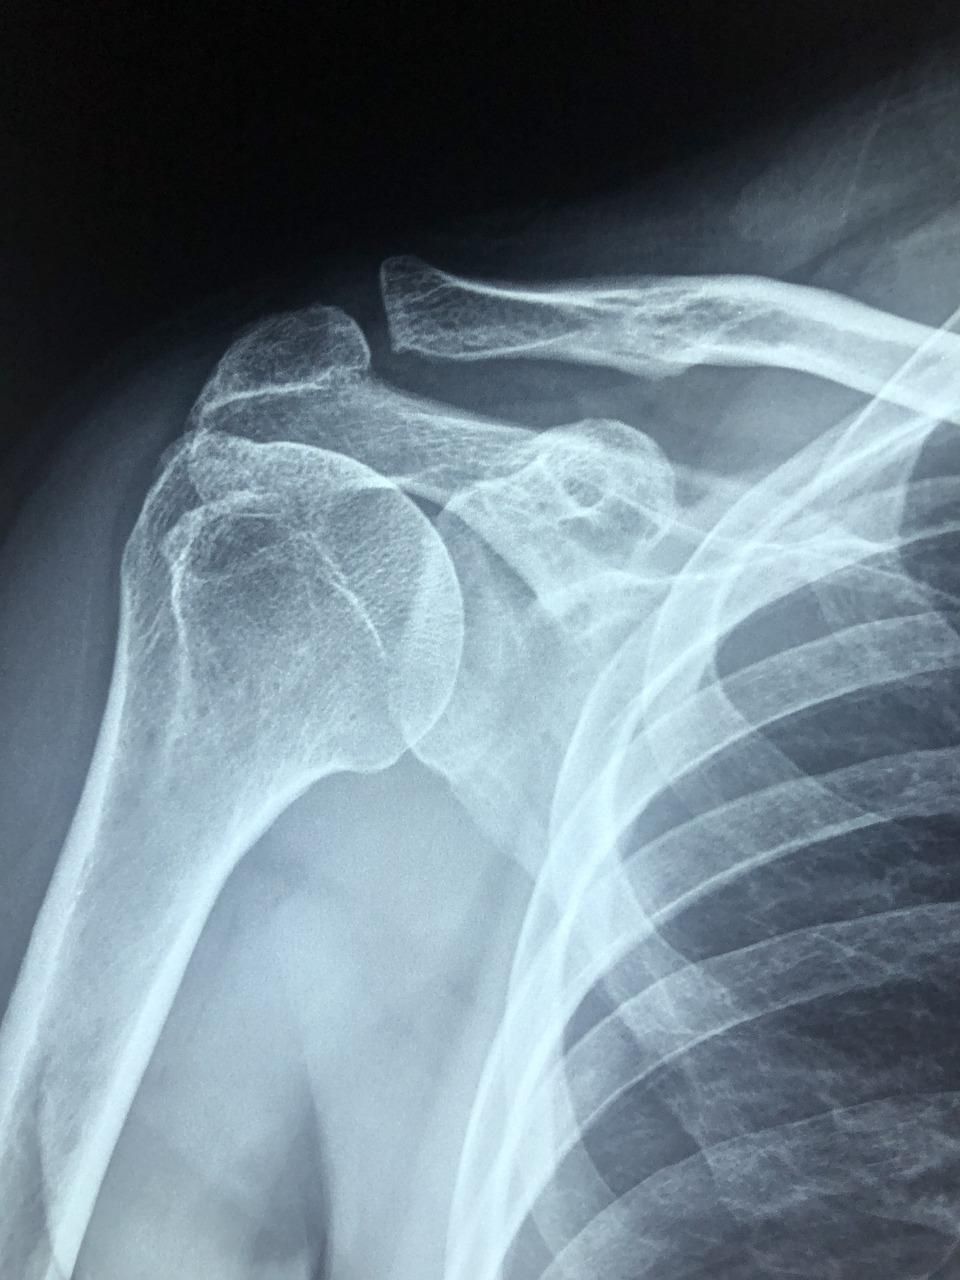

El Dr. López Velázquez es un médico experto y con amplia experiencia en realización de técnicas e infiltraciones ecoguiadas en Madrid Centro. Realiza más de 100 técnicas distintas en todo el cuerpo (hombro, codo, muñeca, dedos, cadera, rodilla, tobillo, pie y también columna).

Estas infiltraciones ecoguiadas son más eficaces que las infiltraciones tradicionales ya que la aguja es guiada a través de una imagen ecográfica hasta el origen del dolor (interior de articulación, tendón, ligamento…) consiguiendo así una máxima precisión y por tanto eficacia.

Las infiltraciones ecoguiadas son necesarias para resolver el dolor de articulaciones profundas como la cadera o de muy pequeño tamaño como la artrosis del pulgar (rizartrosis), por poner algunos ejemplos.